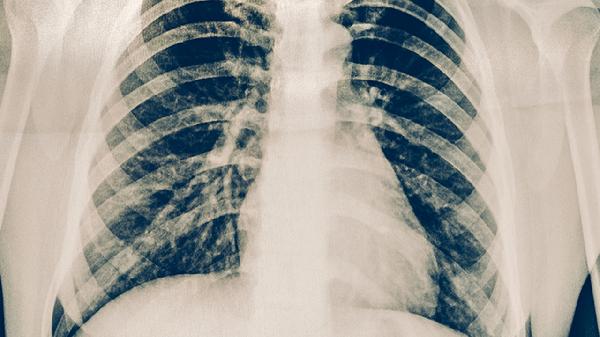

肺部严重感染通常由细菌、病毒或真菌引起,如肺炎链球菌、流感病毒或曲霉菌等。感染范围广、症状重如高热、呼吸困难、低氧血症的患者,病情进展较快,可能短期内危及生命。重症肺炎或急性呼吸窘迫综合征患者需要进入ICU接受呼吸机支持治疗。